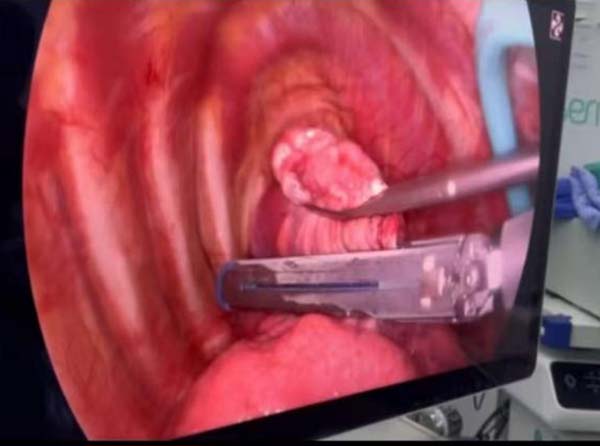

图2 术中团队操作情况

图3 胸腔镜下情况

图4 术中切除标本